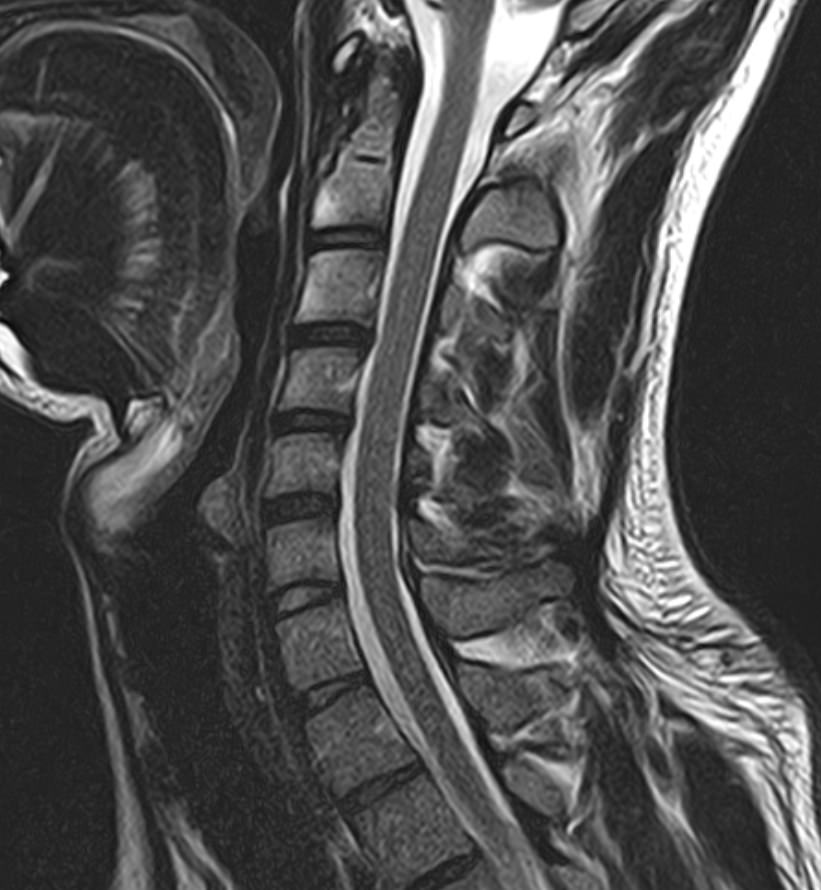

В клинике «Доступная медицина» можно пройти комплексное обследование, включающее в себя несколько протоколов сканирования близко расположенных друг от друга анатомических областей – шейного отдела позвоночника и головного мозга. Метод комплексного обследования оценивает состояние всех структур головного мозга и шейного отдела позвоночника. При этом дополнительные протоколы обследования позволяют визуализировать крупные сосуды шеи и сосудистую сеть головного мозга.

Шейный отдел позвоночника — это самый подвижный сегмент позвоночного столба, который испытывает повышенные нагрузки, подвержен травмам и развитию различных заболеваний. В эту анатомическую область входит 7 верхних позвонков, спинной мозг с отходящими от него нервными корешками.

Кроме того, в области шеи проходят крупные кровеносные сосуды, кровоснабжающие все структуры головного мозга и мягких тканей головы. К ним относятся плечеголовной ствол, сонные и позвоночные артерии, которые далее в полости черепа соединяются между собой в Виллизиев круг. Это анатомическое образование позволяет компенсировать мозговой кровоток при патологических состояниях.

Часто различные нарушения в шейном отделе позвоночника приводят к ухудшению кровоснабжения головного мозга. Опухоли и дегенеративно-дистрофические заболевания шейного отдела позвоночника могут нарушать работу головного мозга. Атеросклеротические бляшки в сосудах шеи могут стать причиной преходящих нарушений мозгового кровообращения (транзиторных ишемических атак) и привести к развитию инсульта. Поэтому важно в комплексе детально визуализировать эти анатомические структуры вместе с оценкой состояния кровеносной системы головы и шеи.

Сканирование проводится на современном высокопольном магнитно-резонансном томографе закрытого типа TOSHIBA VANTAGE TITAN 1,5 Тесла. Магнитно-резонансный томограф производит послойное сканирование исследуемой зоны в разных плоскостях, затем при помощи компьютерных программ преобразует полученные данные в трехмерные изображения. При этом кровеносная система реконструируется как вместе с окружающими тканями, так и отдельно без них.